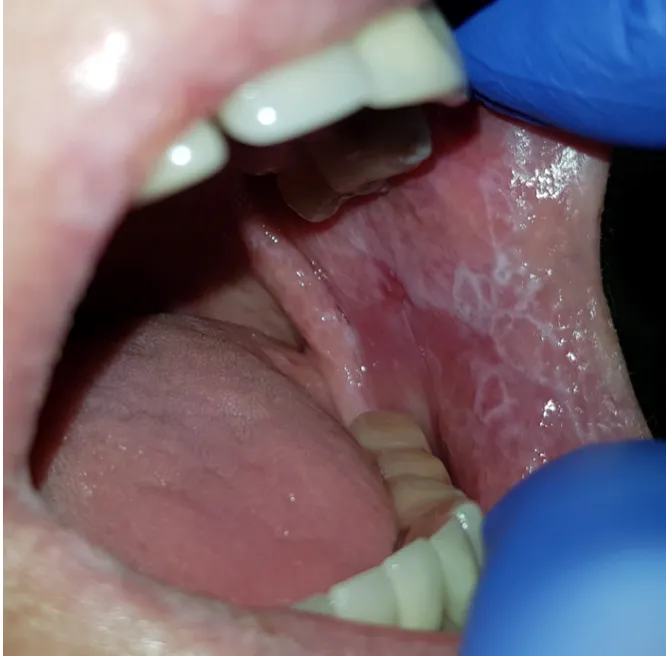

- Postać siateczkowata: Jest to najczęstsza forma liszaja płaskiego. Objawia się białymi, koronkowymi liniami, które często układają się w charakterystyczną siateczkę Wickhama. Zmiany te najczęściej lokalizują się na błonie śluzowej policzków, ale mogą pojawić się również na dziąsłach i języku. Zazwyczaj nie powodują bólu ani większego dyskomfortu, co sprawia, że pacjenci często dowiadują się o nich przypadkowo podczas rutynowej wizyty u stomatologa.

- Postać nadżerkowa/zanikowa: Ta forma jest znacznie bardziej bolesna i uciążliwa. Charakteryzuje się czerwonymi, bolesnymi nadżerkami i owrzodzeniami. Pacjenci doświadczają znacznego dyskomfortu, pieczenia i bólu, który nasila się zwłaszcza podczas jedzenia ostrych, kwaśnych lub słonych potraw. Zmiany te mogą występować w różnych miejscach jamy ustnej, często na języku i wewnętrznej stronie policzków.

- Postać pęcherzowa: Jest to najrzadsza, ale jednocześnie najbardziej dokuczliwa postać liszaja. Początkowo tworzą się pęcherze, które jednak bardzo szybko pękają, pozostawiając po sobie bolesne nadżerki. Ta forma również wiąże się ze znacznym bólem i utrudnia codzienne funkcjonowanie.